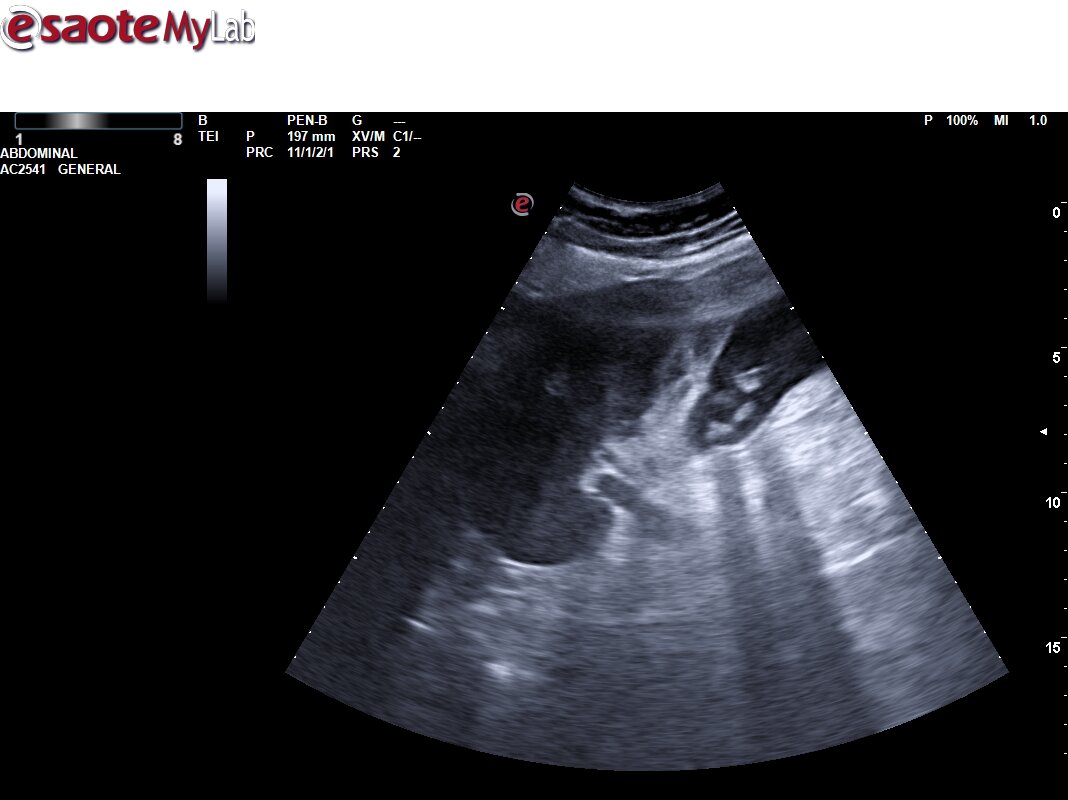

Ecografía Urgencias: Vesícula biliar de tamaño normal, con engrosamiento de la pared con edema de la mucosa. Pequeña colección perivesicular entre la pared vesicular y el reborde hepático de unos 10 mm de grosor, pérdida de continuidad de la pared vesicular compatible con pequeña perforación. Mínima lámina de líquido libre adyacente a la misma. Asocia también abundante contenido hiperecogénico en su interior en relación con barro biliar y varias litiasis en el infundíbulo vesicular. EcoMurphy +. Hallazgos sugestivos de colecistitis aguda complicada con colección / Abceso perivesicular. No líquido libre en los espacios abdominales explorados.